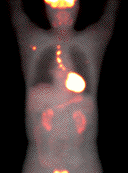

刘某某 男 67岁

2013年8月确诊为原发性肝癌,行手术治疗。

2014年4月16日在家人的搀扶下来到国力医院中医门诊治疗,冉明教授接诊,患者主要症状有:疲乏,胸闷不舒,脘腹、胁肋部胀闷,腰痛,双下肢浮肿,不思饮食。舌淡暗,苔白腻,脉弦细。冉明教授诊断为:肝脾不调,痰湿内停。用中医“状态疗法”对症疏肝健脾,化痰利水治疗。开方1个月,让患者带药回家治疗,并嘱咐患者心情要好,按时服药。

2014年5月28日患者来复诊,仍有疲乏,腰酸的症状,双足水肿,食欲一般,食后腹胀,二便正常。舌淡暗,苔白,脉濡。冉明教授辨证为气血亏虚兼阳虚,痰瘀互阻。以中医“状态疗法”益气养血温阳,祛瘀化痰。鼓励患者坚持治疗可以带瘤生存。患者继续服药至今,目前身体情况基本稳定,定期复查,各项指标都趋向稳定正常水平。